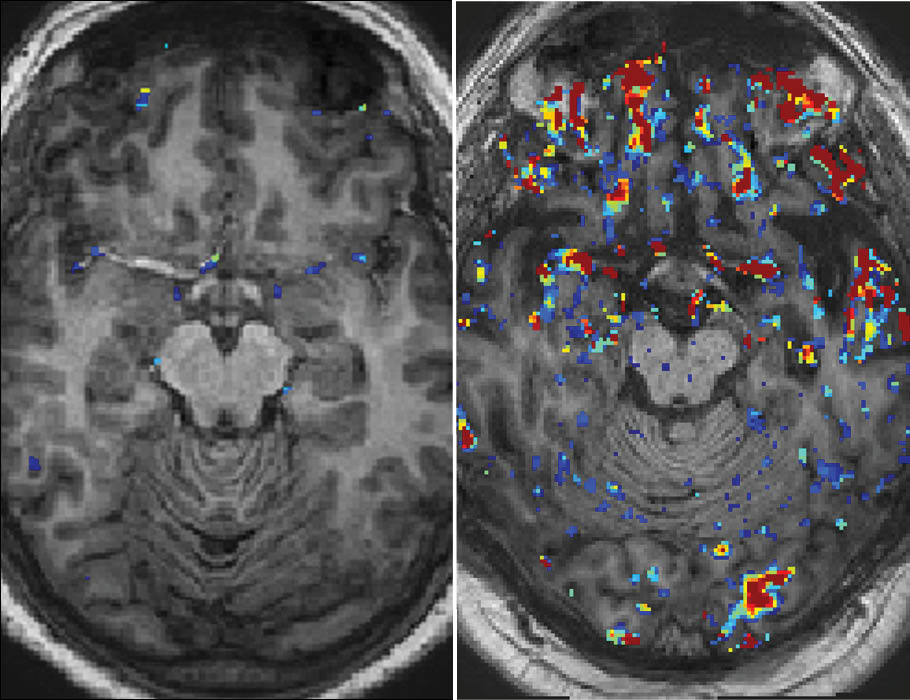

Studies of uterus transplant recipients reveal how immune cells shape pregnancy outcomes, an amino acid cocktail enhances nanoparticle delivery of therapeutic mRNAs in mice, and more this week in #ScienceTranslationalMedicine. scim.ag/3NgmFcX